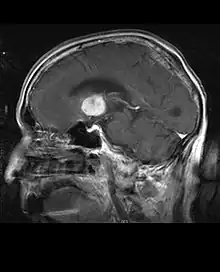

Les patients atteints de méningiome peuvent présenter des symptômes typiques d'une lésion crânienne massive, notamment des convulsions et des déficits neurologiques focaux. détecté sur la tomodensitométrie et l'imagerie par résonance magnétique pour d'autres raisons. Cette tumeur de résonance a un aspect caractéristique, consistant généralement en un rehaussement de contraste uniforme le long de la dure-mère avec une séparation nette du parenchyme cérébral. Une autre caractéristique, bien que non présente dans tous les cas, est la soi-disant "queue durale", représentée par un renflement qui s'étend au-delà de la lésion et indique le point d'ancrage dans la dure-mère.

De nombreux méningiomes découverts fortuitement ne nécessitent pas de traitement au moment du diagnostic initial. Si le patient présente un effet de masse significatif, que les symptômes soient présents ou non, le traitement de choix est généralement complet résection. Dans un studio Mayo Clinics comparant les taux de contrôle des tumeurs après résection chirurgicale et radiochirurgie chez des patients atteints de méningiome intracrânien petit à modéré et sans symptômes d'effet de masse, la radiochirurgie a permis un meilleur contrôle (98 contre 88 %) et avec moins de complications (10 contre 22 %) par rapport à l'ablation chirurgicale.